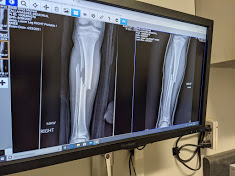

Left: before it got set. Looks a hell of a lot better once he moved most of it back into place. The surgeon is going to put two stainless steel “flex nails” on each side of the bone and get them healing. He opted out of the lifetime steel rod because his growth plate in the knee is still young. He’ll be in a cast for 4 weeks, then a boot, then healed. The nails will stay in until December to be safe. We’re on the road to recovery!

Oh my! That Xray looks awful! Hope your son heals quickly.

oh my goodness – the Xray! My momma heart hurts for you . . .and of course, for him! Wow – that was wonderful to have the doctor and others there to help.

Oh my. I know it must have been so hard to watch your boy go through all this. It was good that all those people were available to help right away. Those x-rays–I’m so glad the second one looks so much better!